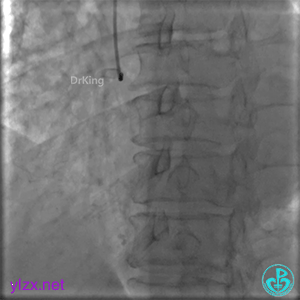

PL分支开口闭塞,PD分支血流3级,开口处可见血栓。

更换6F JR 4.0指引导管,Runthrough NS进入PL分支。

2.0×15mm球囊扩张PL分支开口后PL恢复2级血流。

PL远端血管周围似乎有片状造影剂滞留。